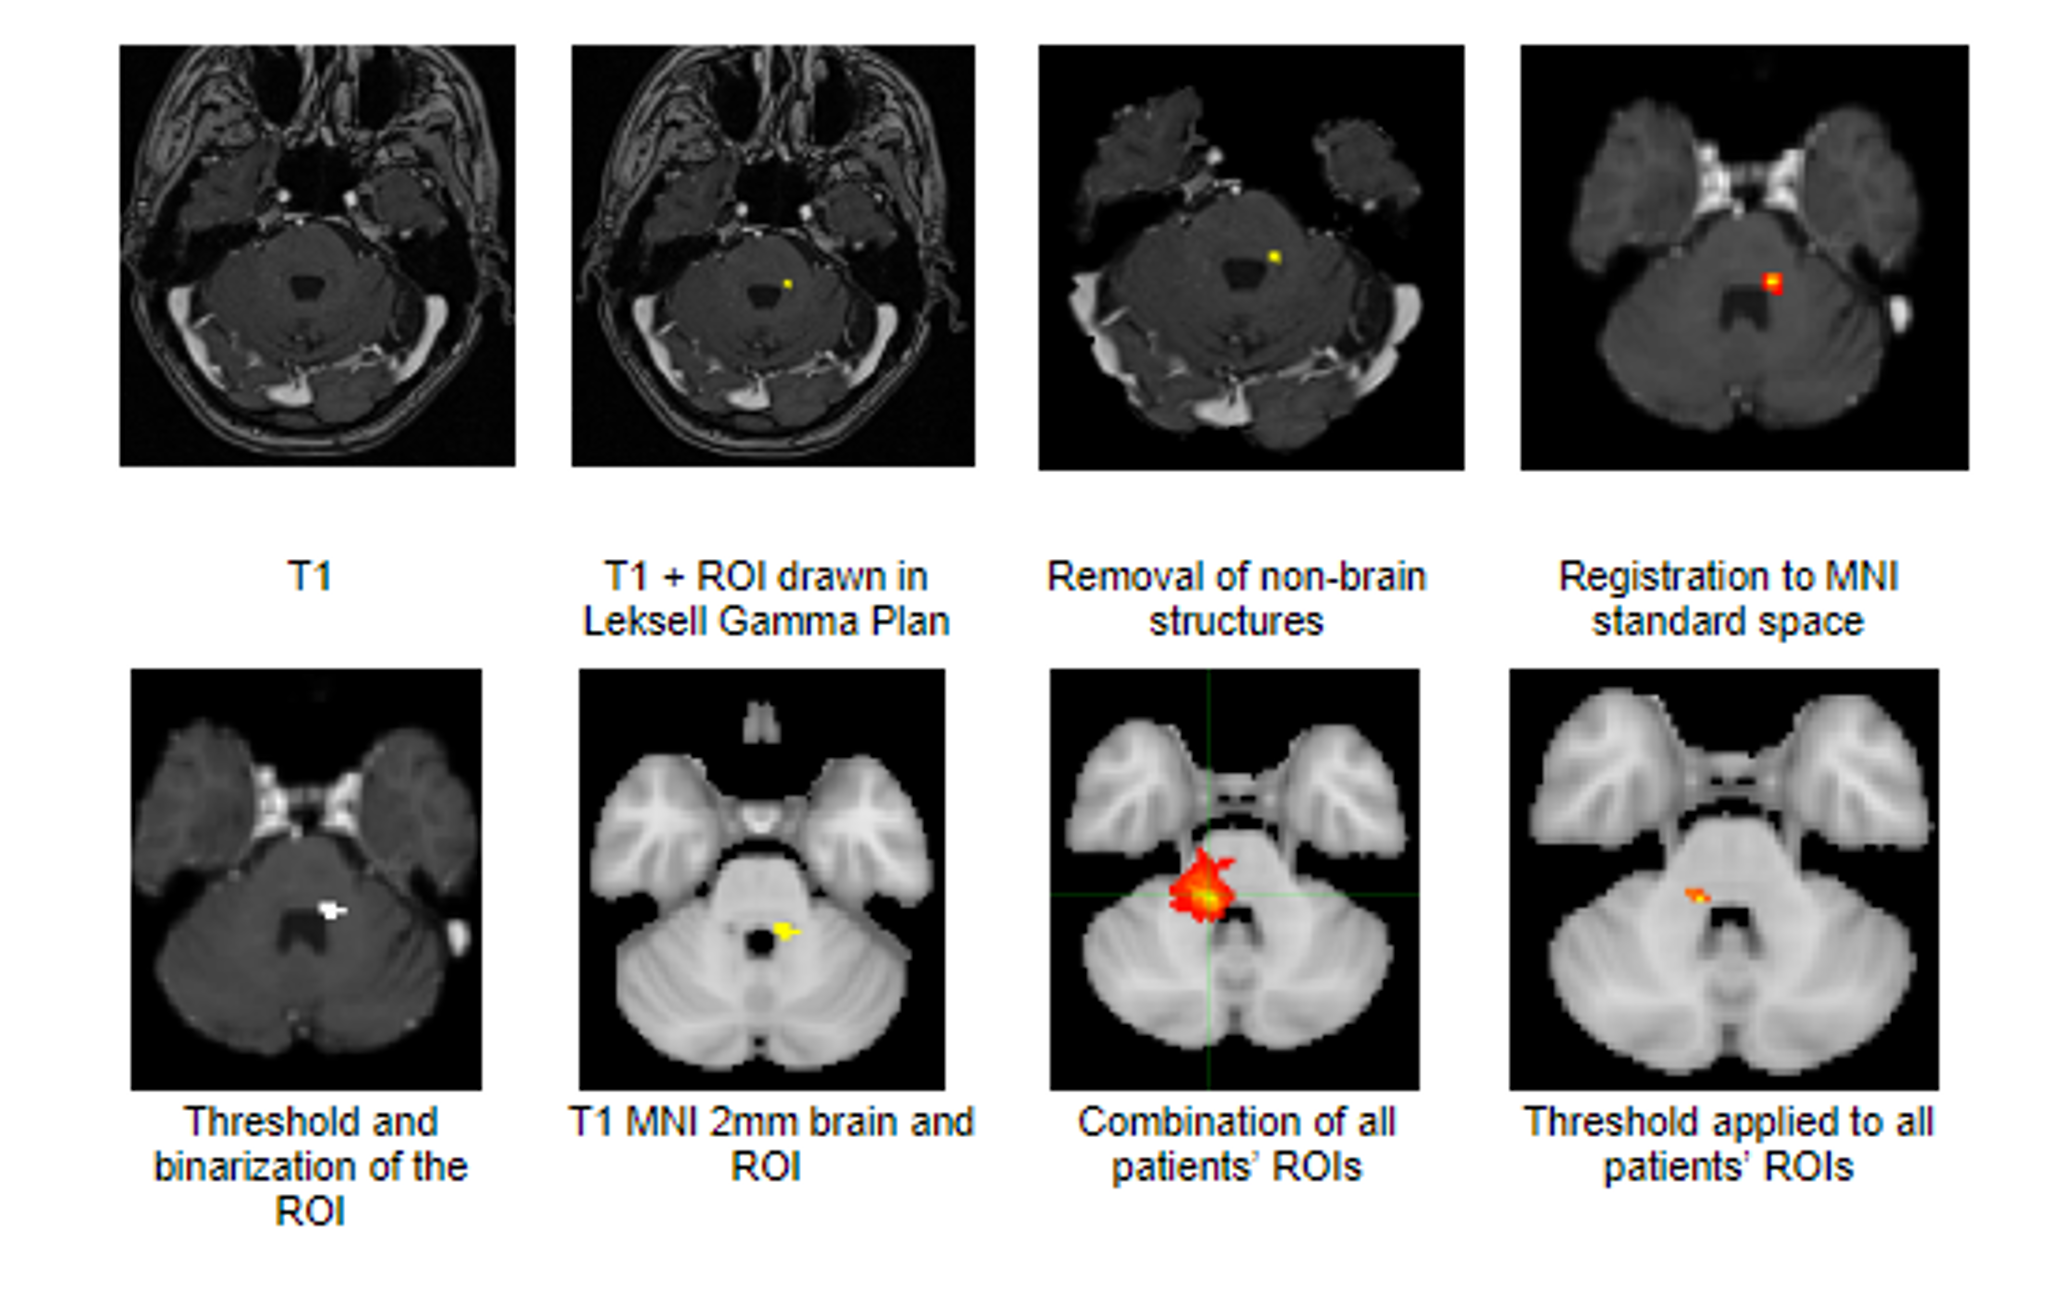

Myelin water imaging in Anti-NMDA receptor autoimmune encephalitis; a pilot study

Background

This study explored whether Myelin Water Imaging could detect myelin injury in Anti-NMDA receptor autoimmune encephalitis (NMDAr-AIE), where traditional neuroimaging is often normal. Myelin Water Fraction (MWF) quantifies myelin content by distinguishing myelin sheath water from other brain water compartments.

Methods

Adult participants with confirmed NMDAr-AIE diagnoses and healthy controls (HC) underwent 3T brain MRI (Magnetic Resonance Imaging) including MWF mapping. Participants were recruited after discharge from the hospital. Mean MWF was calculated for 4 white matter regions of interest (ROI). MHI (Myelin heterogeneity Index) was calculated by dividing the MWF standard deviation by the mean MWF. Patient demographics, clinical assessments, treatment, and outcomes were collected.

Results

Five participants with NMDAr-AIE (4F/1M, mean age 30, SD 7) and four HC (3F/1M, mean age 36, SD 6) were included. All NMDAr-AIE participants had normal or non-specific T2 hyperintensities on initial imaging and had received immunotherapy. The mean Modified Rankin Score (MRS) on discharge was 2. MWF (mean ± SD) for normal-appearing white matter, corpus callosum, corticospinal tract, and superior longitudinal fasciculus were 0.10±0.02, 0.12±0.02, 0.15±0.03, 0.12±0.02, which were very similar to HC at 0.09±0.02, 0.11±0.01, 0.15±0.02, and 0.11±0.02, respectively.

Fig. 1 Myelin Water Imaging of two selected patients

Screenshot 2025 06 01 at 12.05.23 pm

Conclusions and Future Direction

Myelin Water Imaging showed no myelin pathology in five NMDAr-AIE patients, with MWF and MHI values comparable to HC, suggesting that myelin pathways are relatively preserved post-recovery from AIE. Moving forward, we aim to continue recruiting healthy controls, patients post-recovery and those experiencing active disease to determine if there are any MWF abnormalities throughout the disease course. Future studies are needed to assess MWF changes in other antibody-mediated encephalitides.